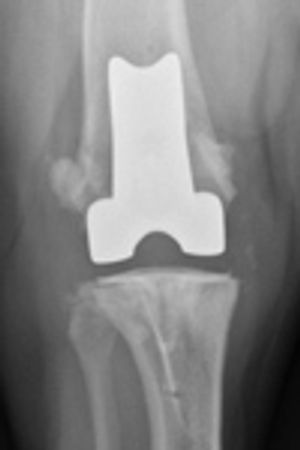

Total knee replacement is a treatment option for nonseptic advanced osteoarthritis and irreparable traumatic injuries when medical management is no longer adequate, reconstructive surgery does not have a good prognosis and arthrodesis and amputation are the other options.